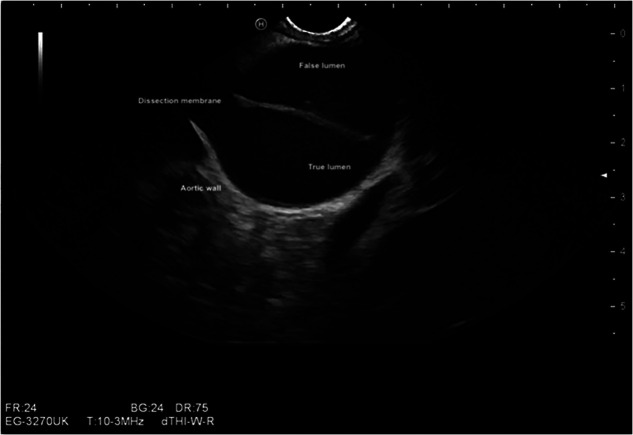

Methods and results: We present six cases of incidentally diagnosed cardiac pathologies (pulmonary thromboembolism of the main pulmonary artery, patent foramen oval with right to left shunt under Valsalva, left atrial appendage thrombus, aortic dissection, moderate aortic valve stenosis, mitral and aortic valve endocarditis) during routine gastrointestinal endosonographic procedures. These diagnoses influenced changes in management strategies in four cases.